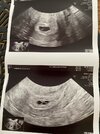

Hej ! My już po wizycie dzisiaj 5+6, wszystko na swoim miejscu - doktor powiedziała ze już nawet widzi bicie serca ! Jestem przeszczęśliwa 🥰 to moja pierwsza ciąża wiec wszystko jest nowe ale myślałam ze pcos wykluczy mnie z bycia mama 🥺 załączam zdjecie tego kilku milimetrowego człowieczka 🥺🥺🤍

• IMG_2026.jpg